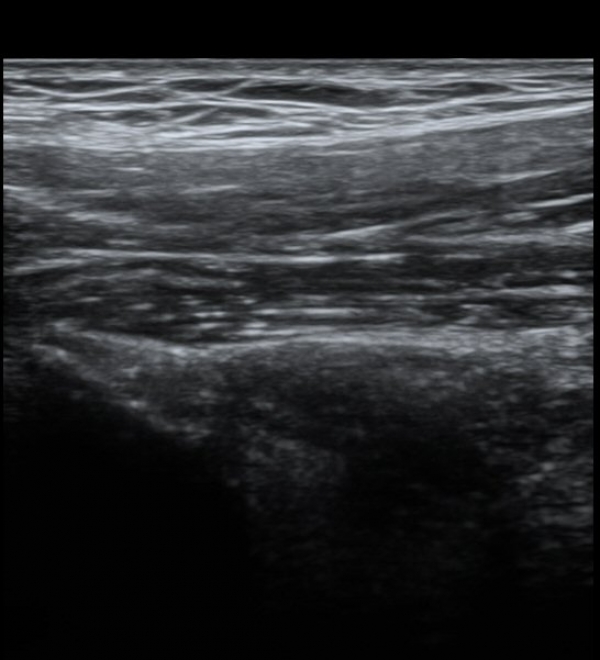

ŽÃËÀÚ¸¦ Á¶±Ý ³»ÃøÀ¸·Î À̵¿ÇÏ´Ï ÈûÁÙÀÇ °í¿¡ÄÚ°¡ ¼Ò½ÇµÇ¾î º¸ÀδÙ(»çÁø 2, 3)